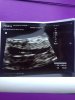

Dziewczyny jestem po wizycie, moja poziomeczka ma 0,5 cm biło serduszko i wszystko ok 😻💖 Jest jedna😁! Mi lekarz wyliczył termin porodu na 26.03.2021, ale ze miewam dłuższe cykle aplikacja pokazuje na 01.04.2021 zobaczymy kiedy maleństwo wyskoczy 🙈 zostanę tutaj z wami:-)! 💖

• 4EC5C1EE-1F2F-47D2-87A6-65C9A5E18B11.jpeg

4EC5C1EE-1F2F-47D2-87A6-65C9A5E18B11.jpeg

1,2 MB · Wyświetleń: 154

Wow super fasolka. Czyli jednak nie bliźniaki [emoji12]